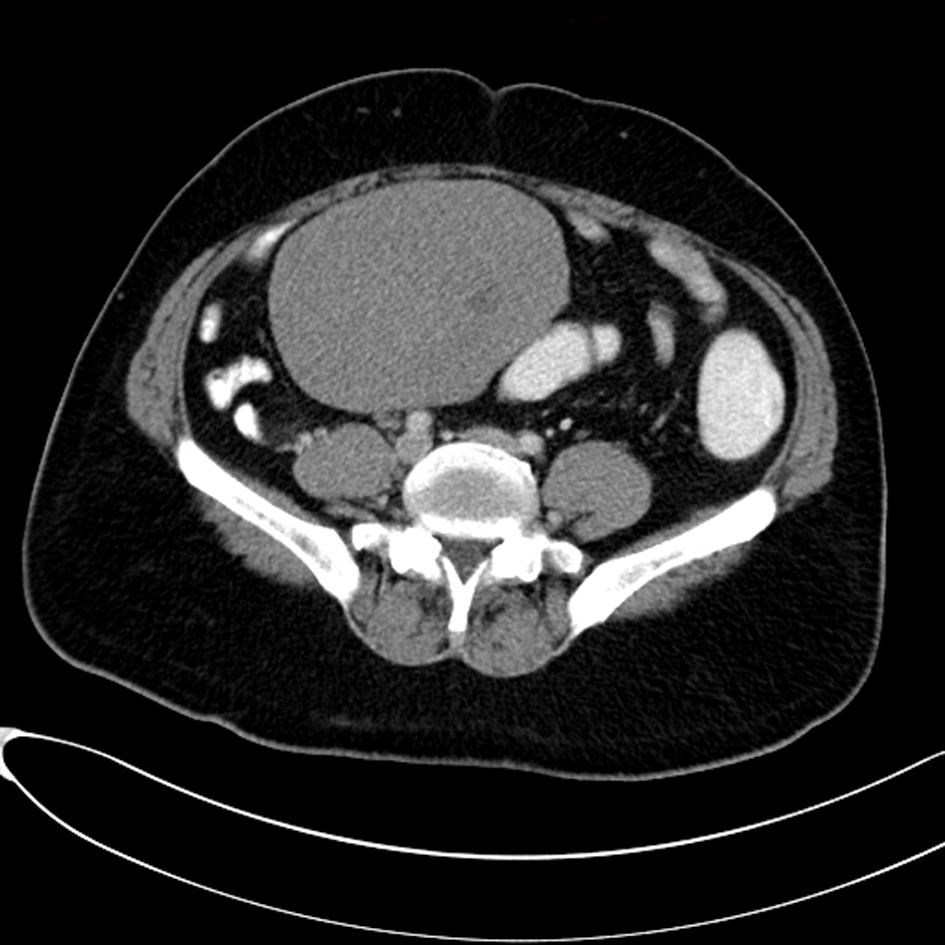

Computed tomography (CT) scan examination of the abdomen and pelvis was performed after administration of intravenous (IV) contrast material in portal venous phase which shows an empty scrotal sac with absence of the testicles and spermatic cord bilaterally (Fig. 1). A large homogenous mass is identified within the retro peritoneum of the right lower abdominal quadrant associated with small central area of low attenuation could represent an areas of cystic necrosis. No associated calcification is seen (Fig. 2). Small oval and homogenous structure is seen within the left aspect of the hemi pelvis just adjacent to the inguinal ring which represents a small atrophied left testicle with no masses (Fig. 3). There are multiple homogenous and matted lymph nodes metastasis located within the right Para-aortic region in close relation to the right renal hilum (Fig. 4).

![]() Click for large image | Figure 2. A large homogenous mass is identified within the retro peritoneum of the right lower abdominal quadrant associated with small central area of low attenuation could represent an areas of cystic necrosis. No associated calcification is seen. |